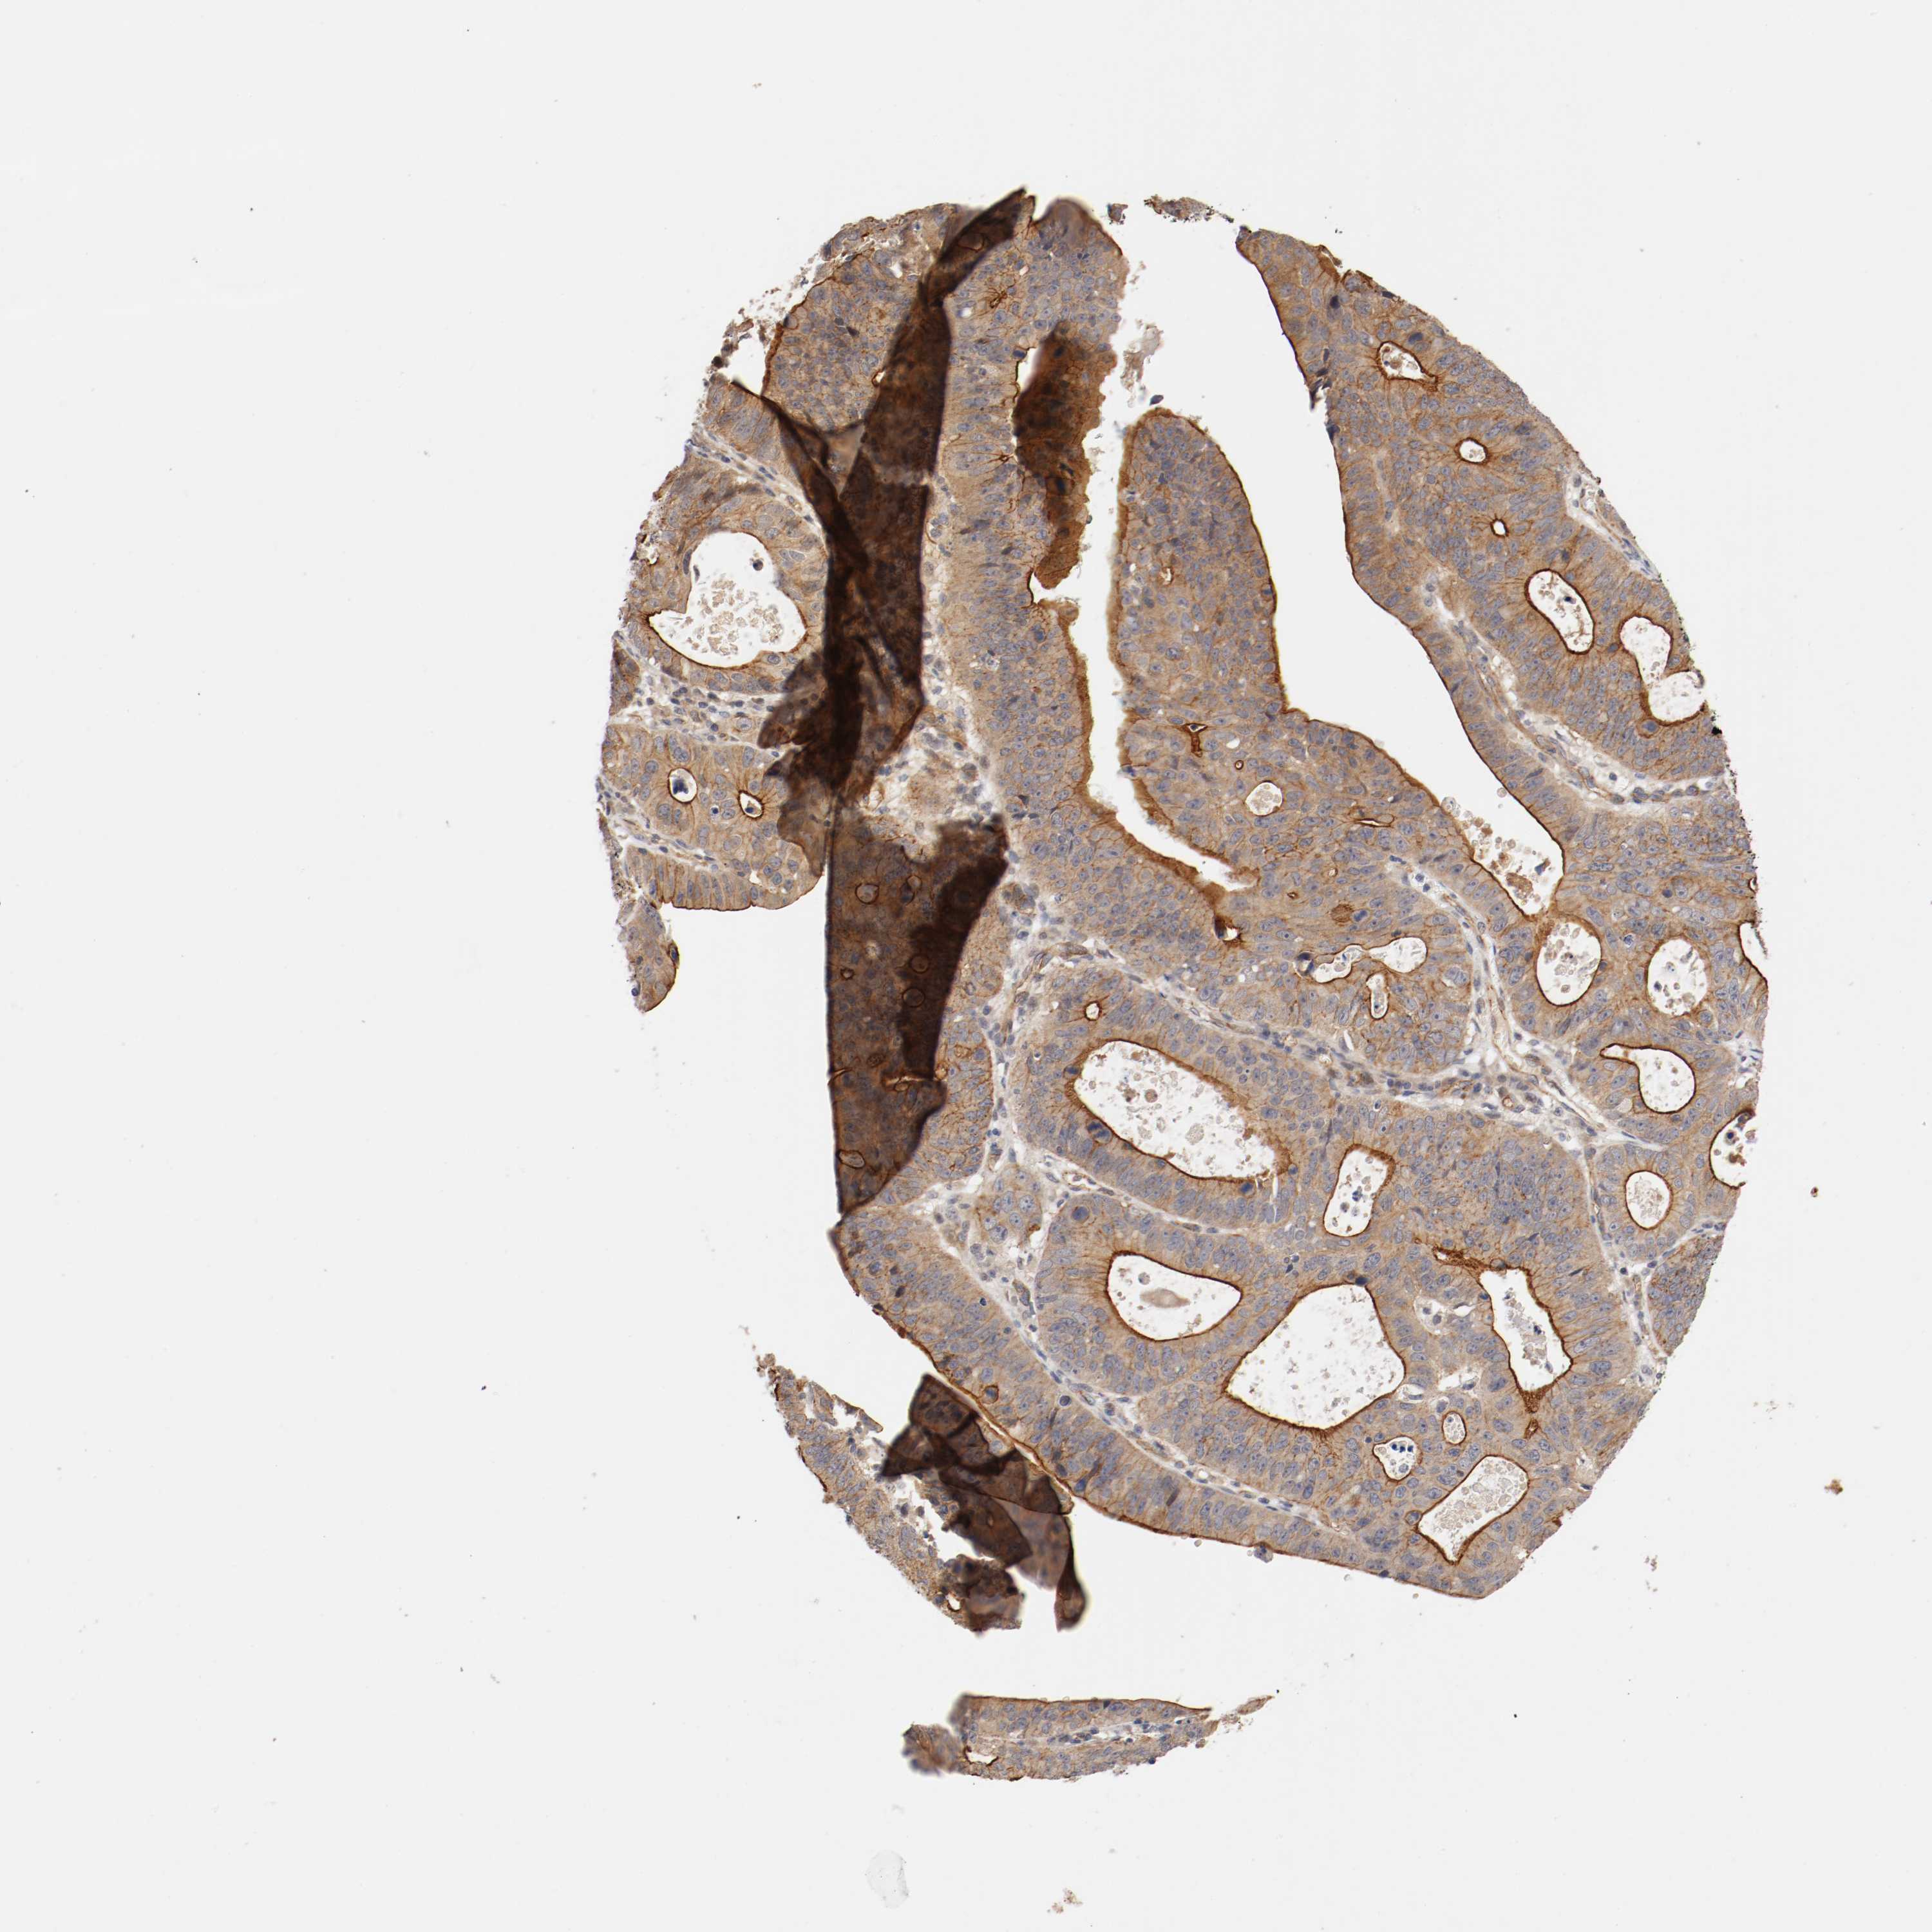

STOMACH CANCER - Protein expressioni

A mouse-over function shows sample information and annotation data. Click on an image to view it in a full screen mode. Samples can be filtered based on level of antibody staining by selecting one or several of the following categories: high, medium, low and not detected. The assay and annotation is described here.

Antibody stainingi

Antibody staining in the annotated cell types in the current human tissue is reported as not detected, low, medium, or high, based on conventional immunohistochemistry profiling in selected tissues. This score is based on the combination of the staining intensity and fraction of stained cells.

Each image is clickable and will lead to virtual microscopy that enables deeper exploration of all samples and also displays staining intensity scores, fraction scores and subcellular localization as well as patient and tissue information for each sample.

Antibody HPA005157

Staining

High

Medium

Low

Not detected

Intensity

Strong

Moderate

Weak

Negative

Quantity

>75%

75%-25%

<25%

None

Location

Nuclear

Cytoplasmic/membranous

Cytoplasmic/membranous,nuclear

Adenocarcinoma, NOS

Adenocarcinoma, High grade